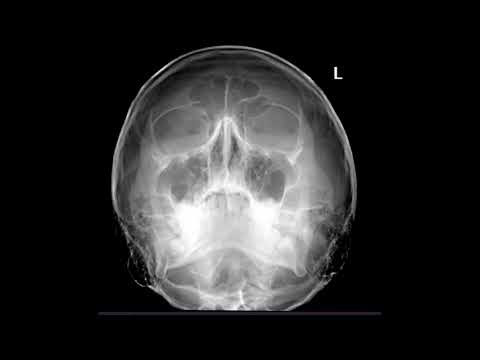

Укладка КТ кисти и лучезапястного сустава